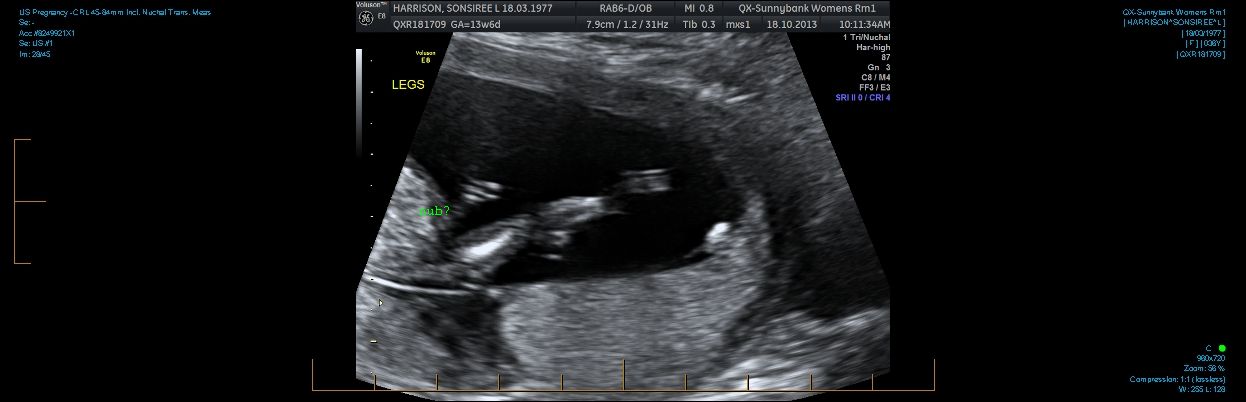

Hi everyone. I am 13w2d and can't figure out if there is a nub in these pics. I also have a potty shot. I know at this age they all have a little something. Can anyone tell me if it is prominent enough to say one way or the other?

Attachment 14828Attachment 14829Attachment 14831Attachment 14832Thanks in advance.